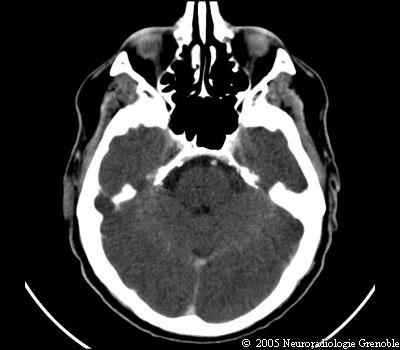

Radioanatomie TDM de l'encéphale

TDM cérébrale sans injection